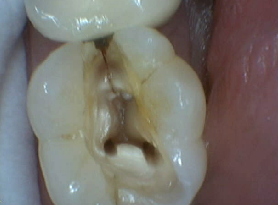

Bruxir Crown, Vertical Fracture, Postop Rot Canal, Fracture Illumination